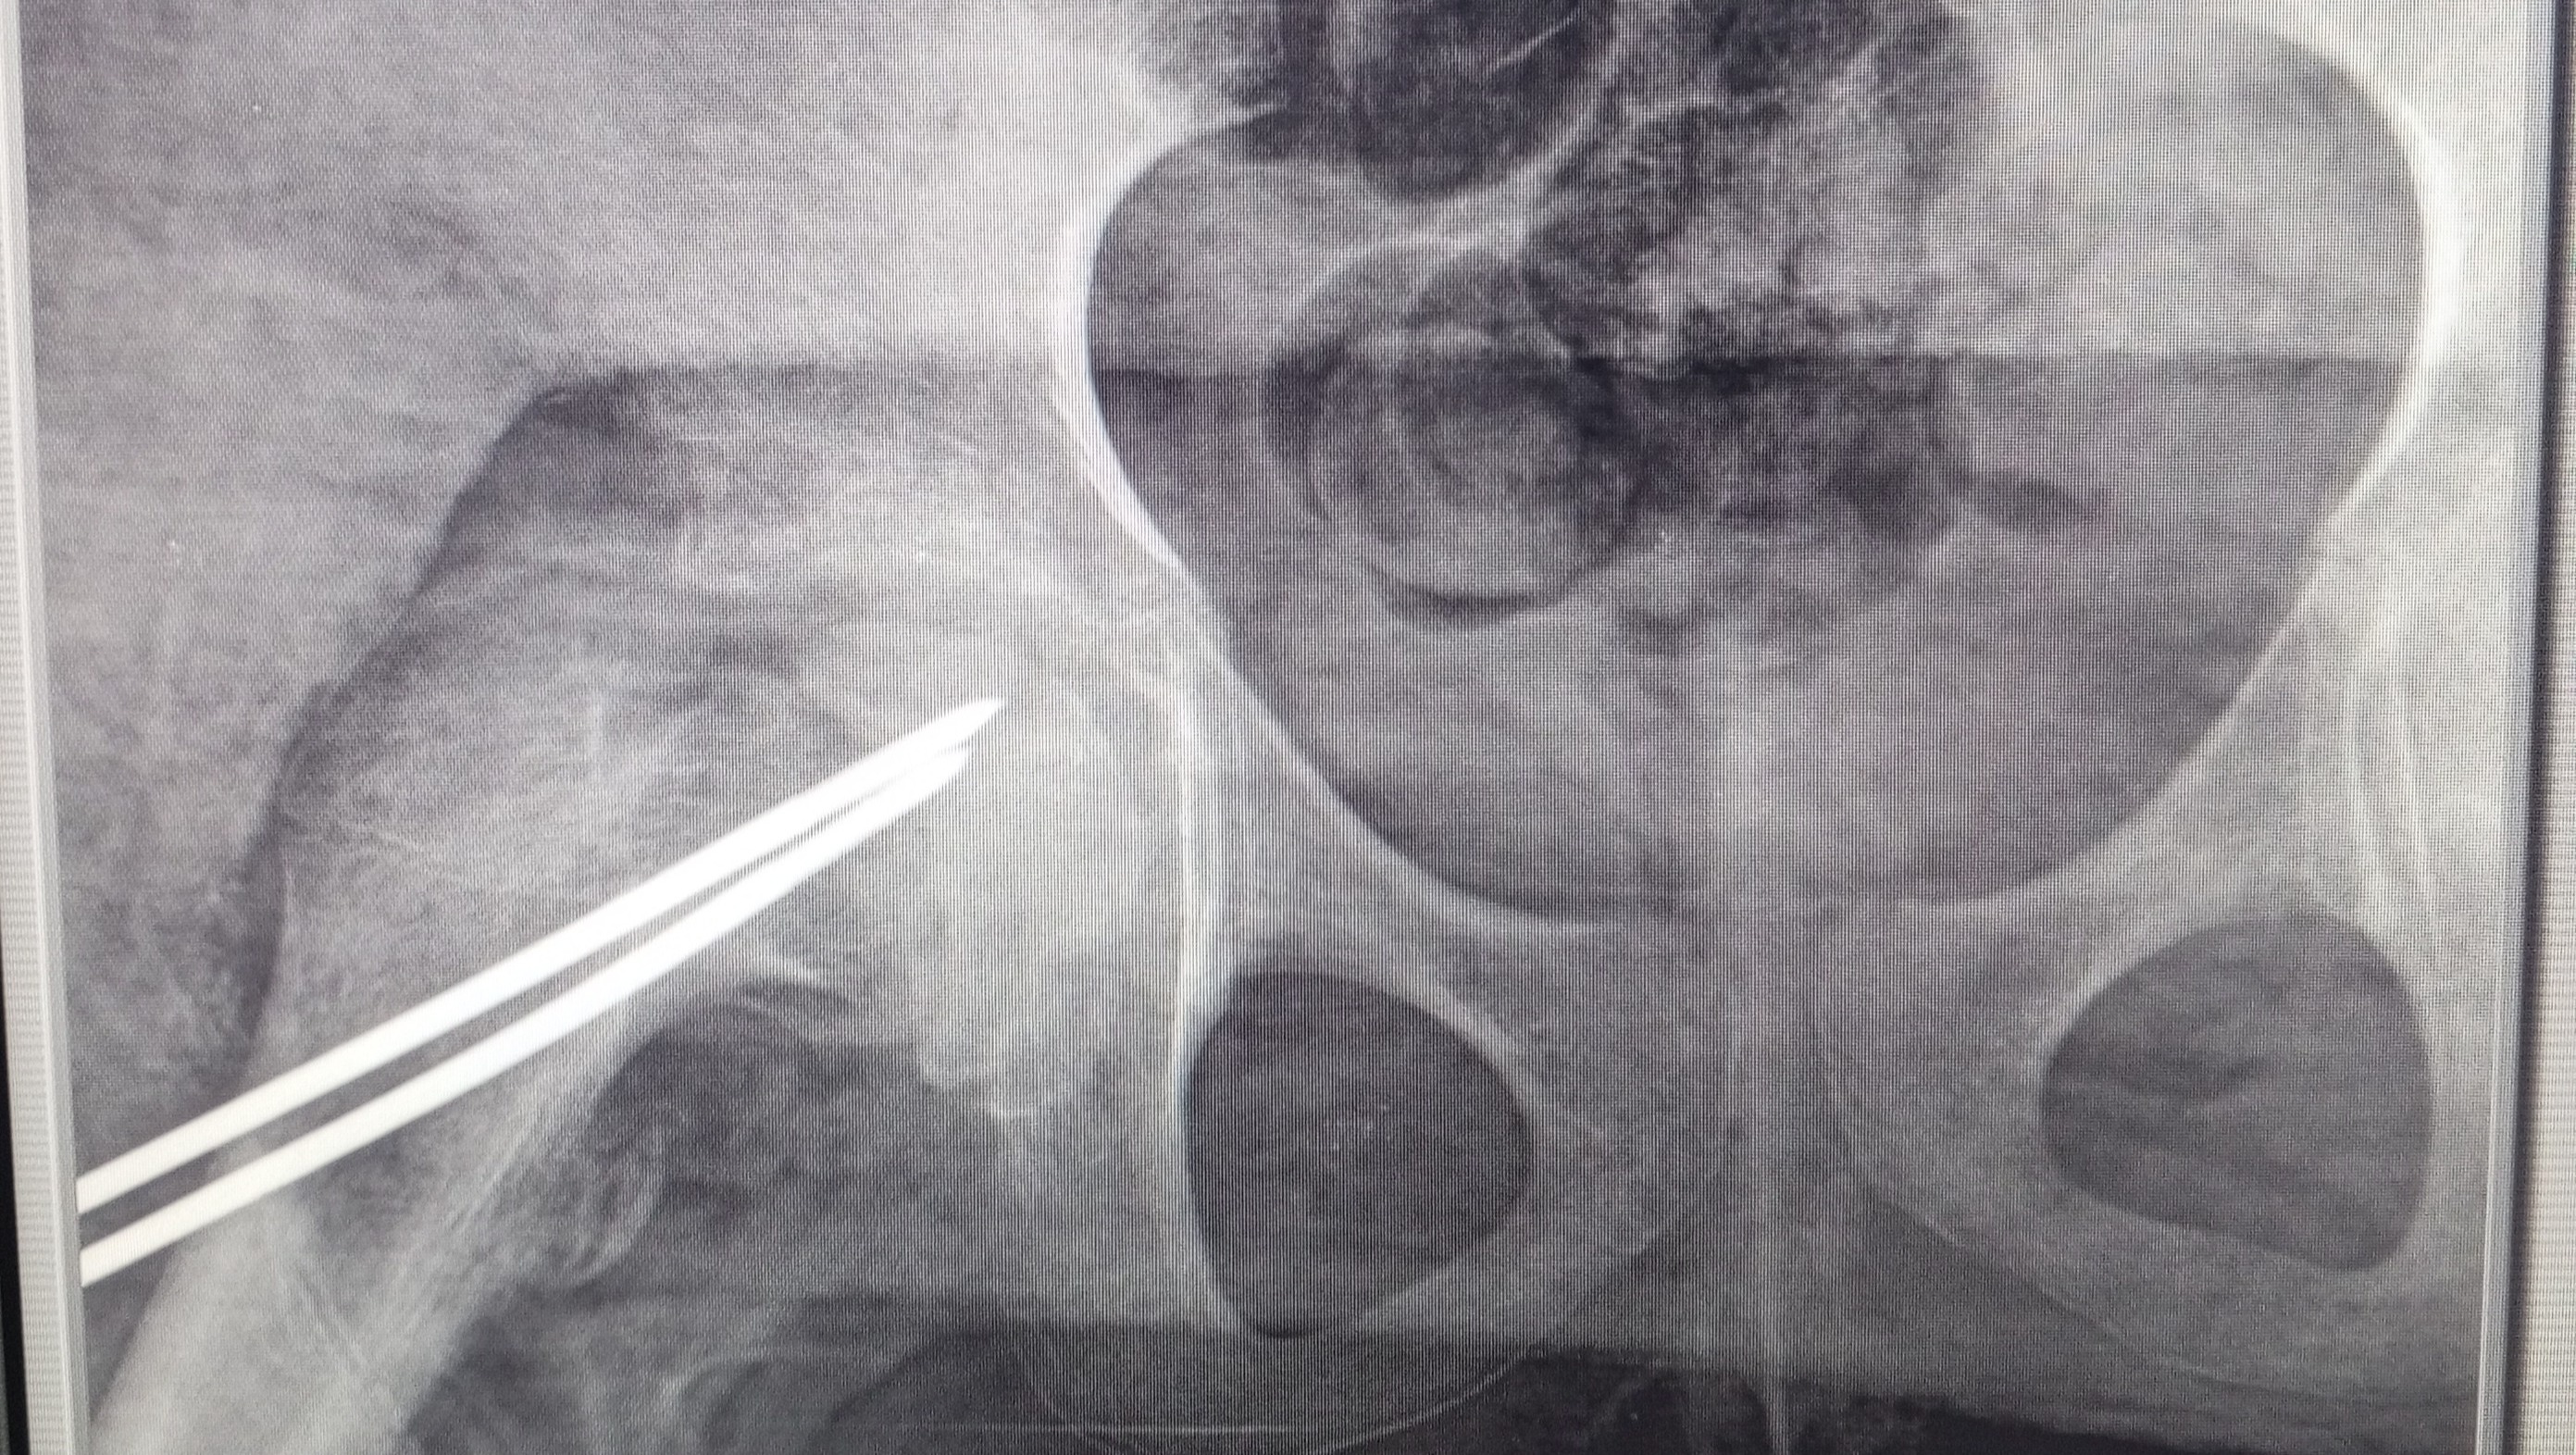

Todo comenzó en mayo de este año, cuando Antonella empezó a quejarse de un dolor intenso en su cadera derecha... No podíamos imaginar lo que estaba por venir. Después de varias visitas médicas y estudios, los doctores nos dieron un diagnóstico que cambió nuestras vidas: un deslizamiento epifisario de la cabeza femoral derecha. Este problema en la cadera limitaba su movilidad y causaba un dolor constante que no la dejaba disfrutar de las cosas simples que a ella tanto le gustan, como jugar, asistir a sus clases o su gran pasión por bailar.

Desde entonces, nuestra familia ha estado en una carrera contra el tiempo. Antonella ha tenido que someterse a dos cirugías en instituciones privadas porque las emergencias no podían esperar y se corría el riesgo de que el área afectada terminara por sufrir una necrosis. Estas intervenciones fueron necesarias para estabilizar su cadera, pero cada una tuvo un alto costo: la primera nos dejó una deuda de USD 2.520 y la segunda de USD 2.000. A pesar de los sacrificios, sabemos que todo valió la pena porque no había otra opción.

Sin embargo, su recuperación aún no ha terminado. Los médicos han indicado la necesidad de una tercera cirugía, ya que lamentablemente la cabeza femoral afectada sufrió una necrosis asintomática, lo que no solo generó un acortamiento de su pierna derecha, sino que también hizo que el material de soporte colocado en la última cirugía se desplazara, comprometiendo seriamente el acetábulo de su cadera. Esta nueva intervención es crucial para garantizar su estabilidad física y prevenir mayores complicaciones. El costo de esta cirugía asciende a USD 2.480, una suma que, sinceramente, no podemos asumir por nosotros mismos.

It all began in May of this year, when Antonella started complaining of intense pain in her right hip. We couldn’t have imagined what was coming. After numerous medical visits and tests, doctors gave us a diagnosis that turned our lives upside down: a slipped capital femoral epiphysis in her right hip. This condition severely limited her mobility and caused constant pain, preventing her from enjoying the simple things she loves—like playing, attending school, or pursuing her passion for dancing.

Since then, our family has been racing against time. Antonella has undergone two surgeries in private institutions because waiting wasn’t an option—the risk of necrosis in the affected area was too high. These procedures were necessary to stabilize her hip, but they came at a steep cost: the first surgery left us with a debt of $2,520, and the second with $2,000. Despite the sacrifices, we know it was all worth it because there was no other choice.

However, her recovery journey isn’t over yet. Doctors have recommended a third surgery as the next crucial step. Unfortunately, the affected femoral head has developed asymptomatic necrosis, resulting in shortening of her right leg and displacement of the support material inserted in the last surgery, which has severely compromised her hip socket. This surgery, essential to ensure her physical stability and prevent further complications, costs $2,480—a sum we cannot afford on our own.